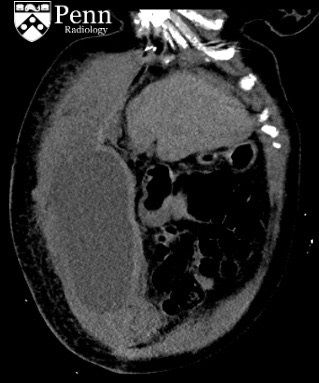

A 45-year-old woman presents with abdominal pain and hypotension. She has a complicated history of cholangiocarcinoma and PE and is currently on anticoagulation. Can you solve this

#radiology case from@PennRadiology? http://bit.ly/381J97U pic.twitter.com/A0vOZqBWPK